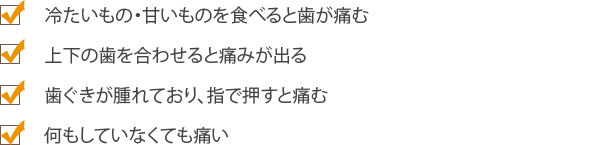

根管治療

虫歯が悪化すると、歯の奥の神経や血管は虫歯菌に冒されて死んでしまいます。そこまで進行した虫歯は、従来では抜くしか方法がありませんでした。しかし、近年では歯をできるだけ残すために根管治療(こんかんちりょう)が行われています。

根管治療の目的

根管治療とは、歯の中にある「根管」という細い管の中から、虫歯菌に冒されて死んでしまった神経や血管を取り除き、内部をきれいに洗浄・消毒して薬剤を充填する治療です。根管はとても細かく複雑に枝分かれしているため、この治療は簡単ではありません。しかし、確実に行えれば歯を残すことができるのです。